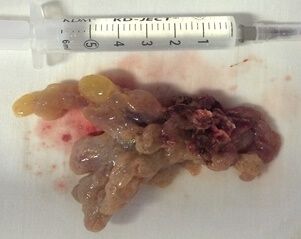

Локализация инвертированных папиллом весьма вариабельна - опухоль может располагаться и на латеральной стенке полости носа в области средней носовой раковины и прилежащих синусов (верхнечелюстной пазухи и клеток решетчатого лабиринта), и на перегородке носа. Инвертированная папиллома, оставаясь гистологически доброкачественной опухолью, по клиническому течению нередко проявляет себя, как злокачественная, поскольку обладает деструктирующим ростом. Она может разрушать костные структуры и прорастать стенки синусов, орбиты, черепа, смещая анатомические структуры и вызывая кровотечения.

Преимущество хирургического лечения в стенах ФГБУ СПб НИИ ЛОР - исключительно эндоназальные эндоскопические доступы в хирургии данных новообразований с максимальным сохранением всех анатомических структур сино-назальной области. Для достижения таких результатов используются различные боры и микродебридеры (шейверы), коагуляторы, эндоскопы с вариабельными углами обзора, навигационные стойки и микроинструменты.